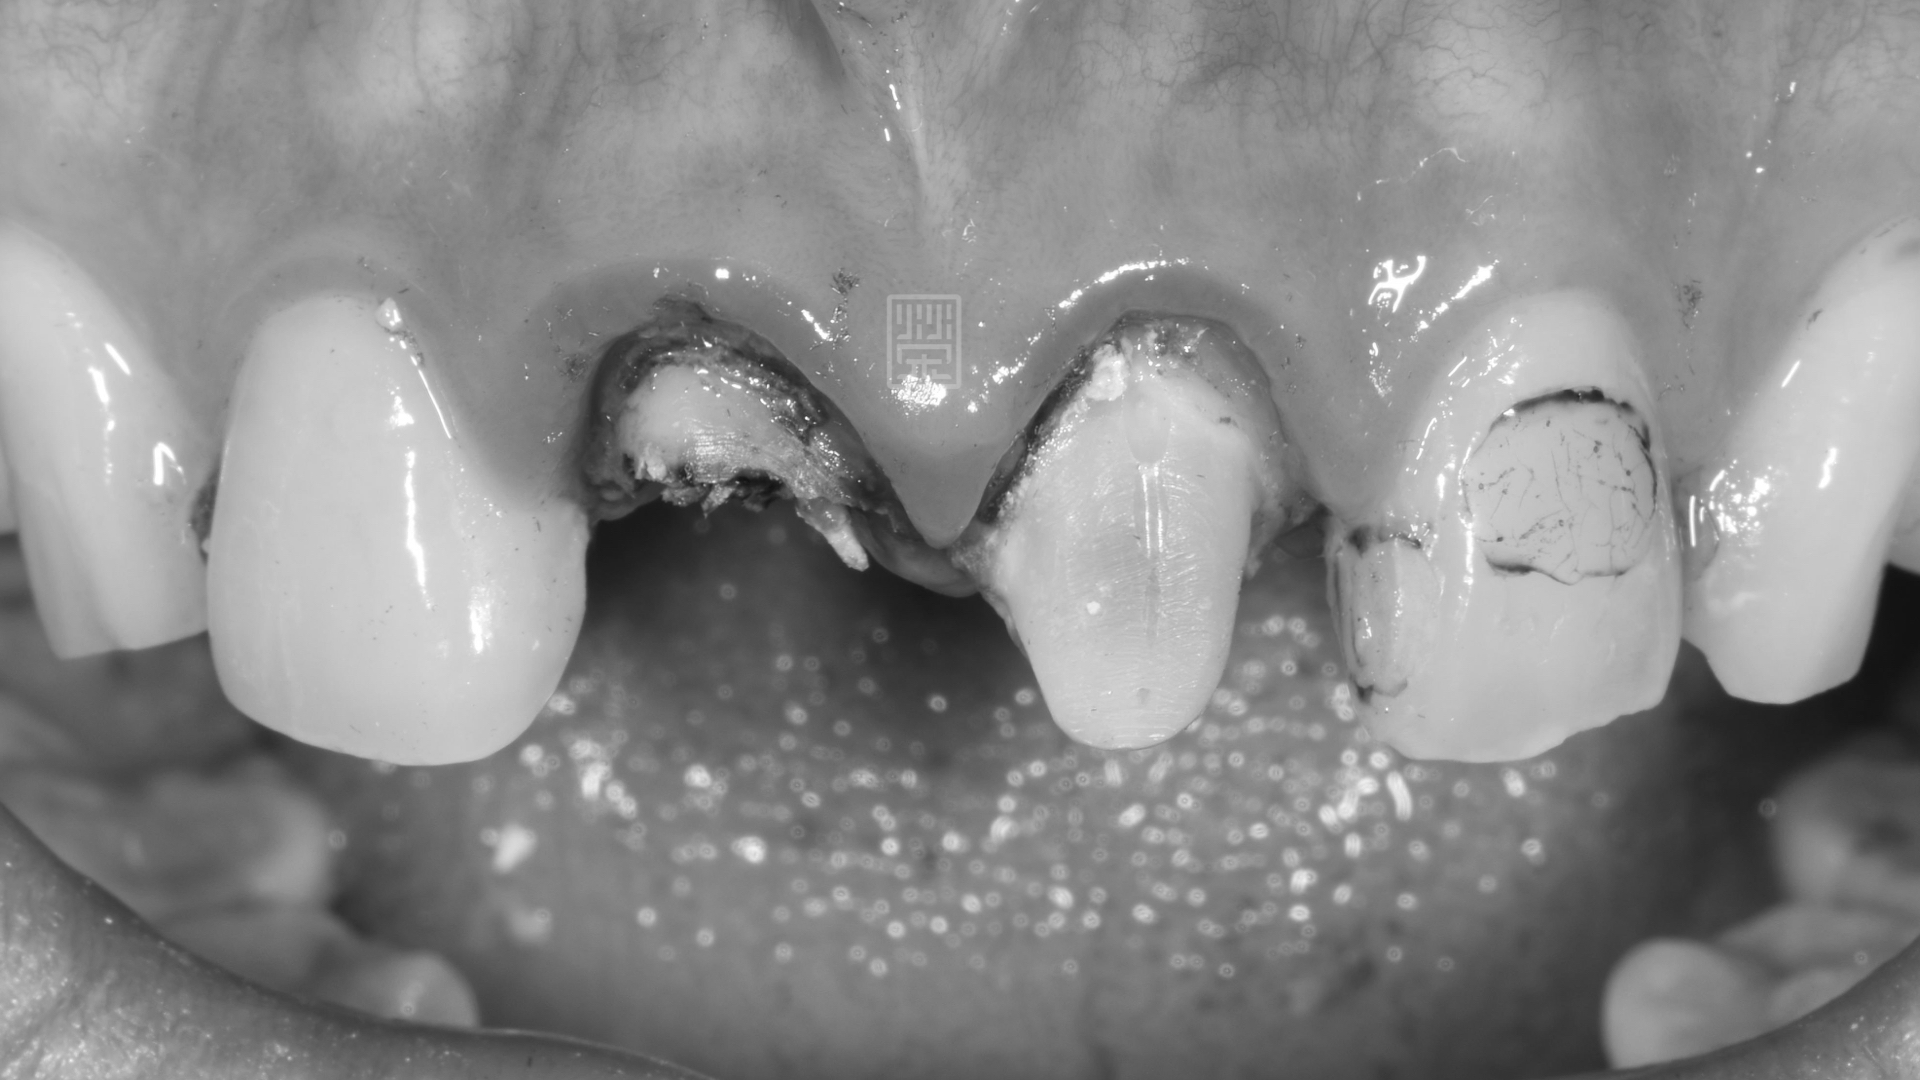

門牙舊假牙有異味

右邊門牙嚴重蛀牙